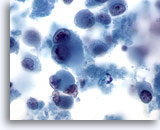

画像 12

肝FNA、肝細胞癌

肝細胞癌からの細胞。肝細胞癌の吸引組織にみる悪性肝細胞。疎性の集塊を形成しています。N/C比が高く、均一に異型が認められます。各肝細胞の間に胆汁色素が認められます。

40倍

画像 12

肝FNA、肝細胞癌

肝細胞癌からの細胞。肝細胞癌の吸引組織にみる悪性肝細胞。疎性の集塊を形成しています。N/C比が高く、均一に異型が認められます。各肝細胞の間に胆汁色素が認められます。

40倍